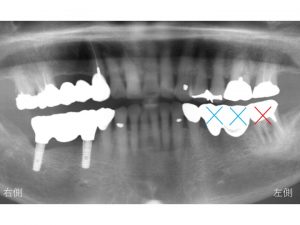

下顎左側は、もともとブリッジという状態担っており、

以下の✖️印が欠損しています。

今回抜歯する歯と合計すると3歯分が欠損していることになります。

このように3歯分が欠損していると何本のインプラントが必要になるのでしょうか?

3歯欠損に対して2本のインプラントを埋入して

3歯分の被せ物を装着する

インプラントブリッジとします。